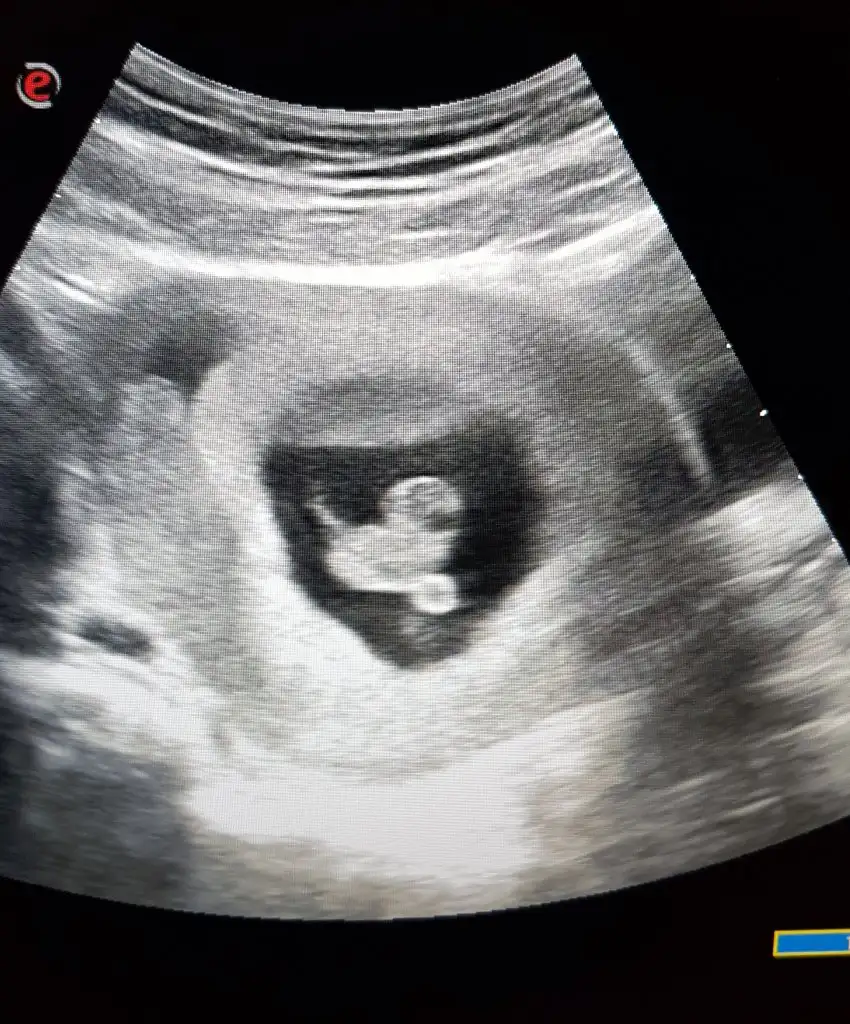

Banada ramzi tahmini yaparmisiniz karindan ultrasyon

Merhaba 👋 karından ultrason 6hafta1 günlük görüntü bu şekilde 🎈bu teoriye göre ne oluyor acaba bilgisi olan yazabilir mi 🙏

Ramzi teorisine göre ( bilimsel bir araştırma sonucuymuş ve %85 doğruluğu varmış). İlk 6-8 haftalık ultrason görüntüsüne göre bebeğin kesenin içersinde soldan ya da sağdan girişine göre cinsiyet tahmini yapılıyor. Bilimsel olunca tecrübeli annelerimiz yada anne adaylarımızdan yardım istiyoruz. Doğruluğu var mı öğrenmek adına :) Bizleri aydınlatırsanız çok seviniriz. bu teorieye göre;

Vajinal muayeneyle bakıldıysa eğer;

Sağdan girmiş gözüküyosa aslında solmuş ve ERKEK,

Soldan girmiş gözüküyosa aslında sağmış ve KIZ ,

Karından bakıldıysa eğer,

Soldan girmiş gözüküyosa gerçektede solmuş ve ERKEK,

Sağdan girmiş gözüküyosa gerçekte de sağmış ve KIZ,